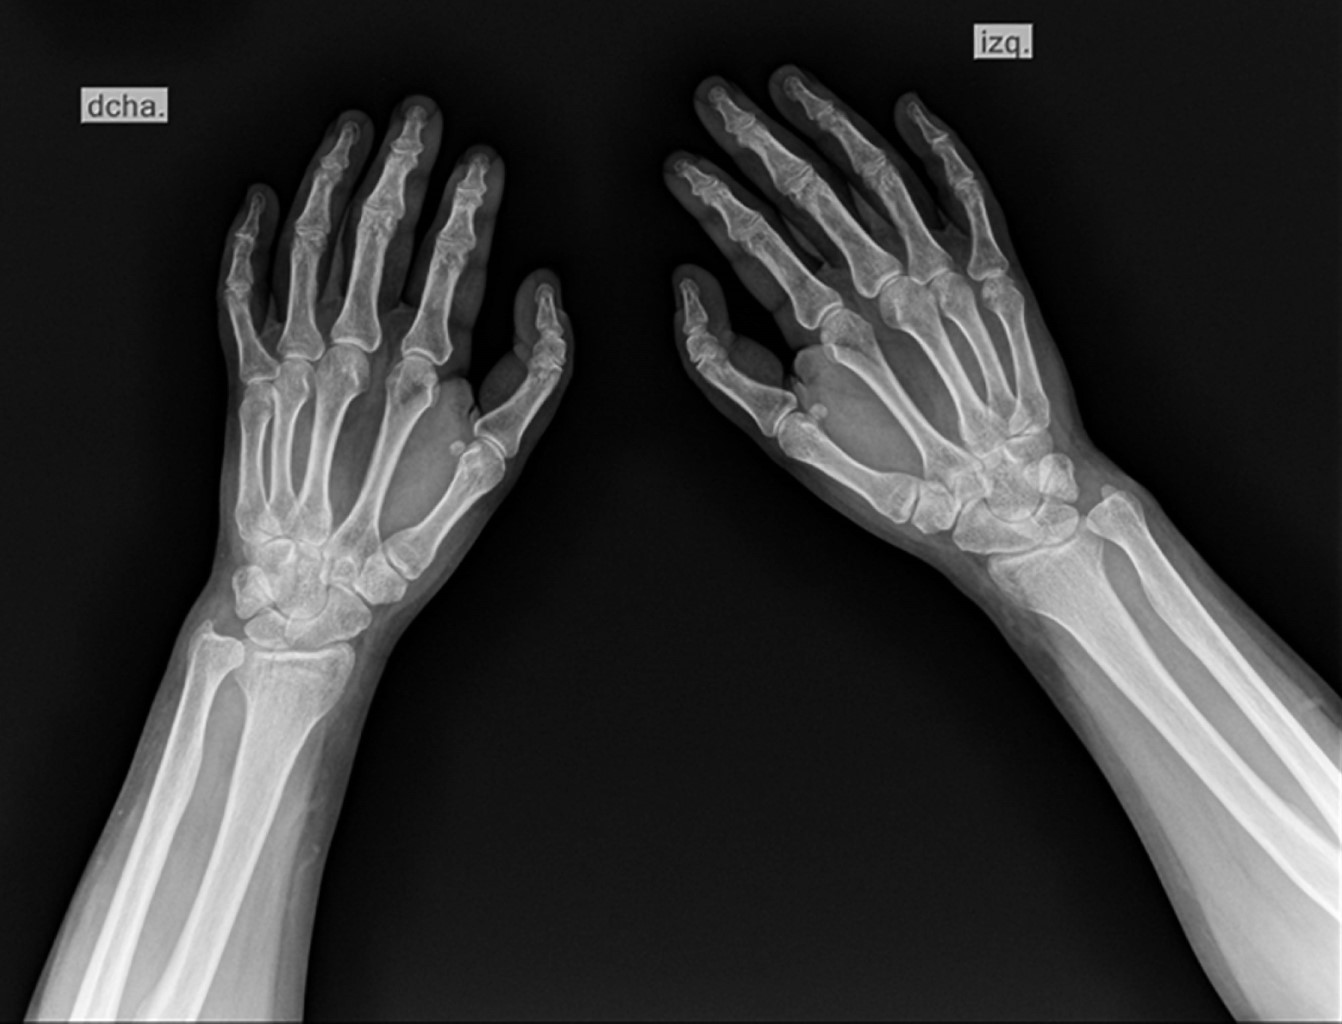

A su ingreso se evalúa por el Servicio de Ortopedia del hospital y se solicitan estudios complementarios por sospecha de fractura. En proyecciones dorsopalmar (Figura 1) y lateral (Figura 2) de ambas manos (con dificultad para su adquisición debido a la limitación de la movilidad por trauma reciente) se evidencia trazo de fractura de la apófisis estiloides de ambas muñecas y de la faceta articular del radio distal bilateral. De forma incidental, se observa pulgar trifalángico bilateral, sin referir sintomatología a este nivel previo al evento traumático.

Figura 2